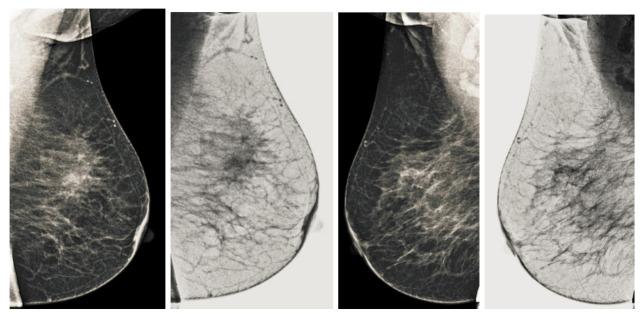

Breast cancer is widespread around the world and can be cured if diagnosed at an early stage. Digital mammograms are used as the most effective imaging modalities for the diagnosis of breast cancer. However, mammography images suffer from low contrast, background noise as well as contrast as non-coherency among the regions, and these factors makes breast cancer diagnosis challenging. These problems can be overcome by using a new image enhancement technique. The objective of this research work is to enhance mammography images to improve the overall process of segmentation and classification of breast cancer diagnosis. We proposed the image enhancement for mammogram images, as well as the ablation of the pectoral muscle. The image enhancement technique involves several steps. In the first step, we process the mammography images in three channels (red, green and blue), the second step is based on the uniformity of the background on morphological operations, and the third step is to obtain a well-contrasted image using principal component analysis (PCA). The fourth step is based on the removal of the pectoral muscle using a seed-based region growth technique, and the last step contains the coherence of the different regions of the image using a second order Gaussian Laplacian (LoG) and an oriented diffusion filter to obtain a much-improved contrast image. The proposed image enhancement technique is tested with our data collected from different hospitals in Qassim health cluster Qassim province Saudi Arabia, and it contains the five Breast Imaging and Reporting System (BI-RADS) categories and this database contained 11,194 images (the images contain carnio-caudal (CC) view and mediolateral oblique(MLO) view of mammography images), and we used approximately 700 images to validate our database. We have achieved improved performance in terms of peak signal-to-noise ratio, contrast, and effective measurement of enhancement (EME) as well as our proposed image enhancement technique outperforms existing image enhancement methods. This performance of our proposed method demonstrates the ability to improve the diagnostic performance of the computerized breast cancer detection method.